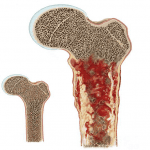

U xơ không cốt hóa (Nonossifying fibroma – NOF) là tổn thương xương thường gặp. Theo như báo cáo xảy ra ở 20% trẻ em và thường mất đi sau tuổi 30. Bệnh thường gặp tuổi thiếu niên, 70% gặp ở tuổi 10-20. Vị trí tổn thương: vỏ xương dài nhất là vùng gần gối (đầu dưới xương đùi, đầu trên xương chày). Không có triệu chứng, phát hiện tình cờ…